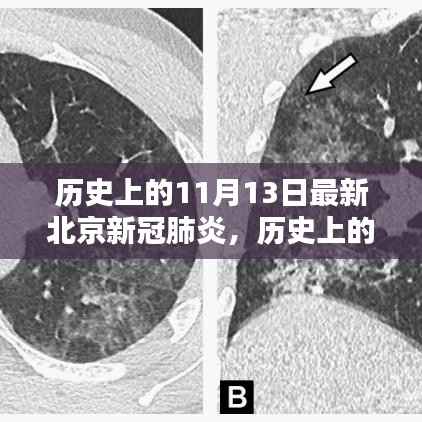

截至最近的数据统计,北京新冠肺炎感染者数量呈现一定的增长趋势,在历史的视角中,每一次的疫情发展都与全球疫情形势紧密相连,随着全球疫情的波动,北京的防控工作面临着新的挑战,在此背景下,北京各级政府高度重视,采取了一系列积极的防控措施。

值得注意的是,北京在疫苗研发与应用方面取得了显著成果,全民接种率的提高,为疫情防控提供了强有力的支持,尽管近期出现了新的疫情高峰,但由于疫苗的保护作用,重症率和死亡率得到了有效控制。